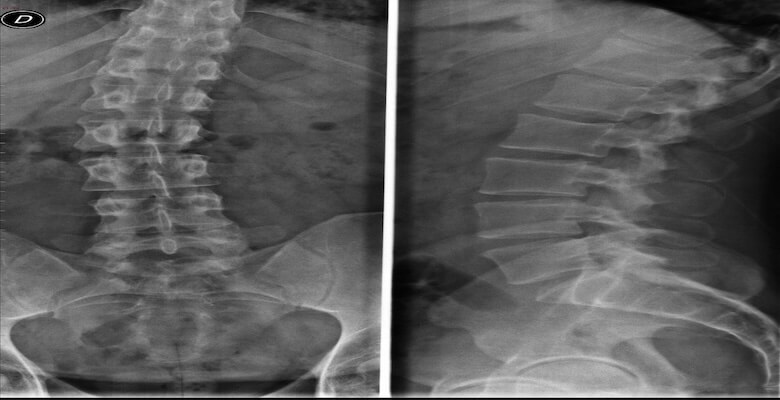

Dar kanal , tıbbi adıyla lomber spinal stenoz, bel bölgesinde omurilik ve sinir köklerinin geçtiği kanalın daralmasıyla ortaya çıkan bir hastalıktır. Genellikle yaşlanmaya bağlı dejeneratif değişiklikler sonucu gelişir ve yaşam kalitesini ciddi şekilde etkileyebilir.

Dar kanal, omurlar arasındaki disklerin yıpranması, faset eklemlerde büyüme ve ligamentum flavum adı verilen bağ dokusunun kalınlaşması sonucu oluşur. Bu daralma, omurilikten çıkan sinir köklerine baskı yaparak şu şikâyetlere yol açar:

Yaş ilerledikçe görülme sıklığı artar. Yapılan çalışmalara göre dar kanal toplumun yaklaşık %11’inde, klinik başvurularda ise %25–39 oranında görülmektedir.